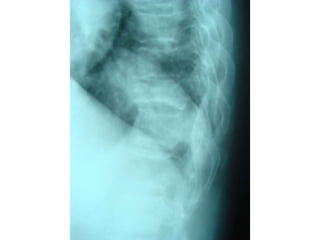

charcot joint

charcot joint by dr khaled abdelbaky